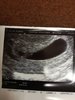

Super!Ja już po USG, w pierwszej chwili się zestresowałam, bo ukazał się wielki pęcherz ale w środku nic, to prawie na zawał zeszłam. Na szczęście lekarz znalazł zarodek schowany z bokuSerduszko pięknie puka, prawie 1cm ma mój Bobolek. Dostałam skierowanie na wszystkie badania, po świętach będę robić. Z USG wychodzi 7t1d ciąży, a z OM 7t2d więc rośnie wręcz idealnie

Ten pęcherz tylko jakiś wielki nie uważacie? Lekarz mówi że to nic niepokojacego że ma po prostu duży domekMoże dlatego mi tak brzuch wywala i mam wzdjęcia bo mnie rozepchało jak nie wiem. Kupiłam po lekarzu w H&M dwie pary spodni ciążowych i chyba już na święta będę chodzić :/ Fajne promki trafiłam, jedne kosztowały 40zł, a drugie 60zł, obie przecenione z 149zł

Już po. Jest 0.55 cm pęcherzyk. Nawet krnąbrny mąż się wzruszył a jak u Ciebie??? W ogóle u Was wszystkich mamusieTy tez napisz po wizycie !

Gratuluję z całego serca dwóm serduszkom!!!!!!!Ja już po USG, w pierwszej chwili się zestresowałam, bo ukazał się wielki pęcherz ale w środku nic, to prawie na zawał zeszłam. Na szczęście lekarz znalazł zarodek schowany z bokuSerduszko pięknie puka, prawie 1cm ma mój Bobolek. Dostałam skierowanie na wszystkie badania, po świętach będę robić. Z USG wychodzi 7t1d ciąży, a z OM 7t2d więc rośnie wręcz idealnie

Super gratulacje!Już po. Jest 0.55 cm pęcherzyk. Nawet krnąbrny mąż się wzruszył a jak u Ciebie??? W ogóle u Was wszystkich mamusie